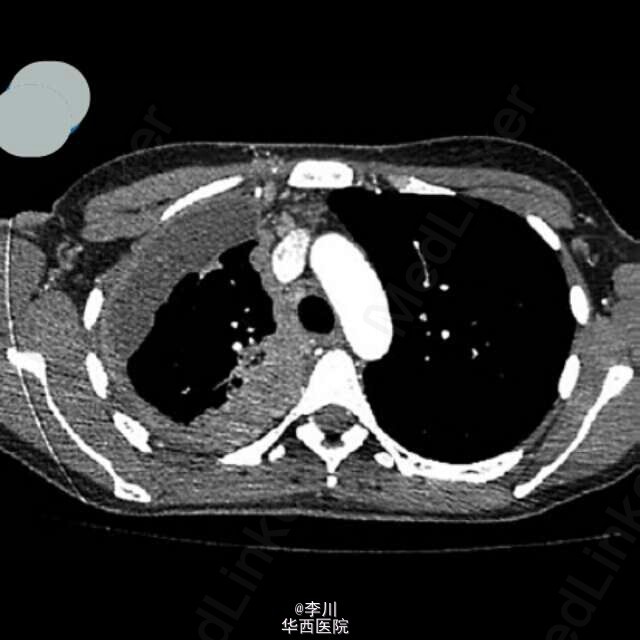

患者女性,38 岁,肺腺癌,年吸烟量 15 包。胸部 CT 表现右上肺脊柱旁肿物。胸膜活检病理证实为乳头状肺腺癌。头颅磁共振显示除灰质外,大脑皮质,基地核和丘脑 粟粒状结节。可以媲美粟粒性肺结核Dziadziuszko K, Szurowska E, Pienkowska J, et al. Miliary Brain Metastases in a Patient with ROS1-Rearranged Lung Adenocarcinoma: A Case Report[J]. Journal of Thoracic Oncology, 2014, 9(5): e34-e36.